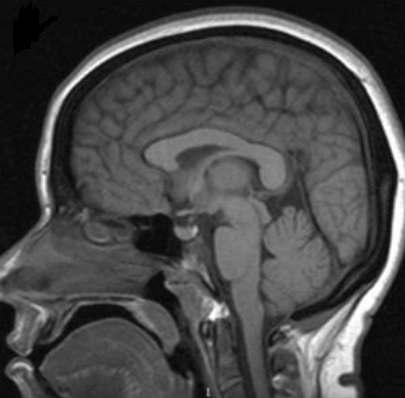

脊索瘤普通放疗能控制多久?一般来说,很少单纯用放疗去治疗脊索瘤,都是多方法综合治理,单纯普通放疗其控制效果并不好,在剂量为40至60 Gy的5年内,控制率仅为10%至40%。这主要是因为脊索瘤需要高剂量(≈70 Gy)的辐射,由于脊索瘤一般靠近辐射敏感结构(如脊髓、脑干、脑神经),这种高剂量辐射会长期性地损伤正常组织,从而限制了提供生物合适剂量的能力,而没有明显的毒性。质子治疗的出现,使人们能够在保留周围正常结构的同时,对肿瘤进行更高剂量的辐射治疗。质子治疗使用的是高能质子束,以较高的速度射入人体,当质子束进入人体后,大部分能量会沉积在射程末端形成尖锐的剂量峰,称为Bragg峰。通过调整可以使Bragg峰在特定深度、准确覆盖整个肿瘤靶区,并将全部能量释放到癌变部位,准确杀伤肿瘤而不损伤周边的正常组织,从而达到更好的治疗效果。总的来说,对于脊索瘤,局部控制以粒子为基础的质子放射治疗在五年内控制率是50%到60%。目前几大质子治疗中心都分布在日本、美国、德国等发达国家。而德国慕尼黑质子中心(RPTC)作为欧洲一家治疗肿瘤的治疗中心,有着不可忽略的优势。也是质子治疗中心之一。

目前对于脊索瘤的治疗,很少单一的使用一种方法治疗,都是多学科的综合治疗。其治疗效果也是优于单一治疗的,目前手术切除加上辅助放疗已经成为脊索瘤的标准治疗。根据美国SEER数据库1973年~2003年间的 414例脊索瘤病例,术后中位生存时间75个月,肿瘤发生转移后生存时间明显下降至24个月, 整块切除+辅助放疗的5年和10年生存率分别为62-67%和40-45%。而在1990年至2011年期间的相关文献统计,有45名脑脊索瘤患者接受了手术切除加放射治疗,从一开始手术到一开始手术的中位时间为13个月(平均34.3个月,2-110个月)。在随后几年的回访中,这45名脑脊索瘤患者,5年和10年生存率分别为67%和57%.5年和10年无进展生存率分别为58%和44%,

脊索瘤的预后如何,手术切除率是关键因素,根据目前循证医学的证据,尽可能地完全切除肿瘤仍然是优选的治疗方式。由于脊索瘤的局部侵袭性较强,因此在手术切除过程中要尽量将肿瘤作为一个整体地切除,而不让肿瘤细胞有任何外溢。由于脊柱周围有脊髓、神经根、大血管、食管、器官、肠道等诸多重要的组织器官,因此达到这样的切除范围是不易的,普通神经外科医生一般是脊索瘤束手无策,所以需要有经验、和技术高超的医生。虽然一般的医生确实对脑脊索瘤束手无策,对INC国际神经外科医生集团旗下国际神经外科顾问团成员Sebastien Froelich教授却并不是难事,教授以颅底手术闻名于世,他对于脊索瘤、脑膜瘤、垂体瘤、颅咽管瘤等都有大量的临床治疗经验,提出了克服脊索瘤的颅底基础方法、鼻内镜和下鼻甲联合皮瓣修复扩大鼻内入路后大面积颅底缺损的手术方法,特别对于脑脊索瘤有很高的切除率。对于脊索瘤神经内镜手术技术,Sebastien Froelich教授发明内镜手术“筷子”手法,让原本需要两个医生配合才能操作的神经内镜手术,在“筷子”手法下,仅一个医生就可以独自进行手术,不止提高了肿瘤的切除率,更是使肿瘤患者有了更好的预后效果。